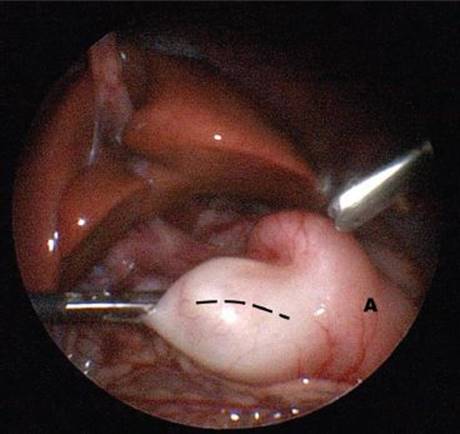

General anesthesia is induced and the infant is placed transversely on the operating table. The monitor is placed at the baby’s head, across from the operating surgeon, who stands at the infant’s feet. An incision is made through the umbilicus or inferior to it. The Veress needle is then placed into the peritoneal cavity through this incision. A 4-mm trocar is inserted after inflation and a 4-mm, 30° scope is inserted. The abdomen is insufflated to 8 to 10 mm Hg. Two 3-mm trocars are then inserted in the right and left epigastrum under direct visualization. The proximal duodenum is grasped with the left hand and an arthrotomy knife is used to incise the serosa of the pylorus (Figure 4). The same landmarks are used for the pyloric incision. A laparoscopic pyloric spreader is used to spread the deep muscular layers (Figure 5). Again, the stomach should be insufflated with the duodenum occluded to evaluate for mucosal perforation. The carbon dioxide is then evacuated from the abdominal cavity, and the umbilical fascia and the skin are closed. The epigastric incisions can be closed with steri-strips or Dermabond.

FIGURE 4 • Serosal incision on pylorus (dashed line) during laparoscopic pyloromyotomy, carried proximally onto the antrum of the stomach (A).